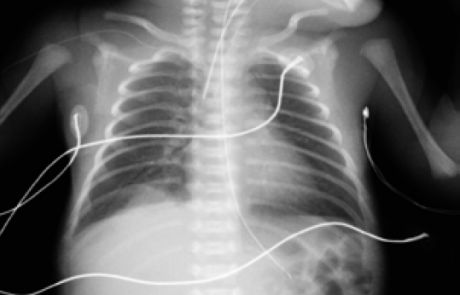

Durante su estancia en la Unidad se realizó una radiografía de tórax al ingreso (figura 1) y controles ecográficos seriados (figuras 2 y 3) en los que se objetivó la lesión quística en la base del pulmón derecho. Se mantuvo una actitud expectante dada la estabilidad clínica del paciente.